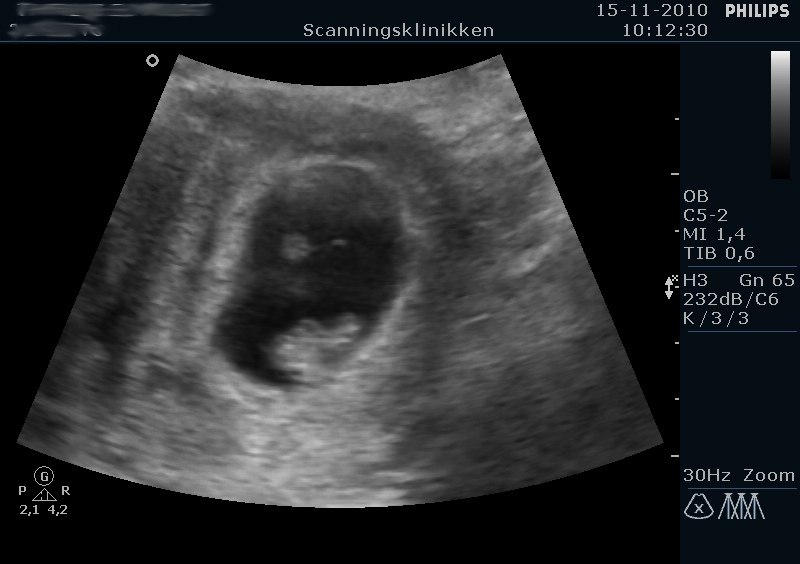

Neders ser I spunken, og på det ene billede er der foroven i det "sorte hulrum" en lille rund prik. Det er blommesækken, som spunken lever af indtil 11. uge ca. Sjovt.